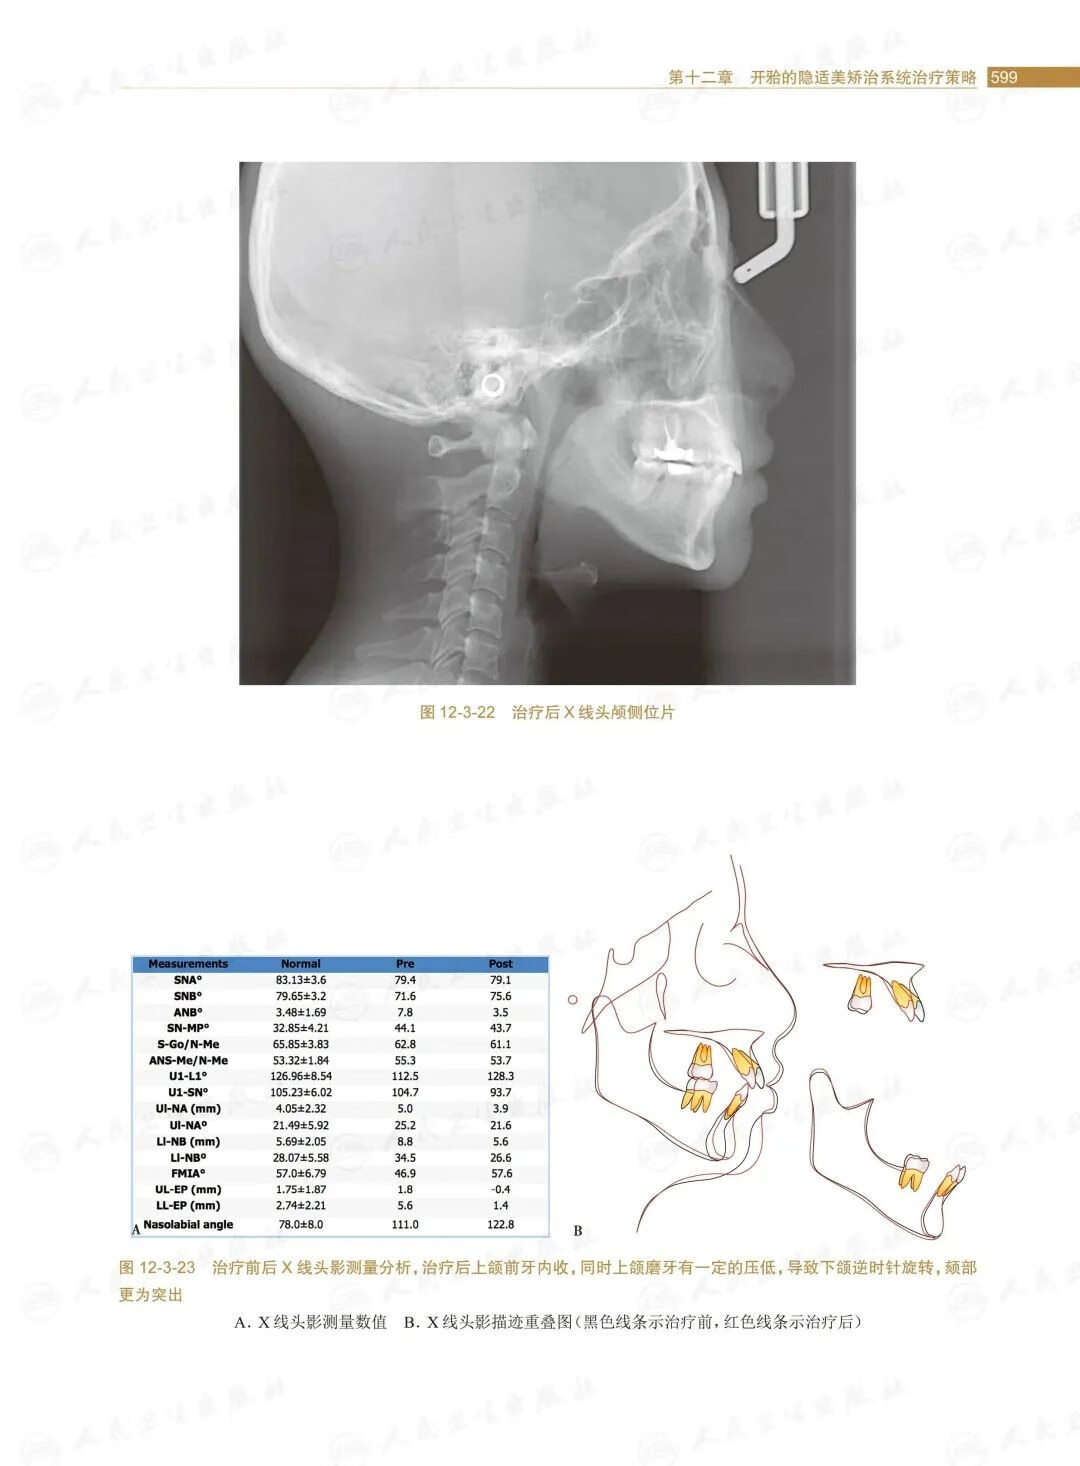

第十二章開的隱適美矯治系統治療策略/.569

第三節安氏Ⅱ類開的矯治策略/588